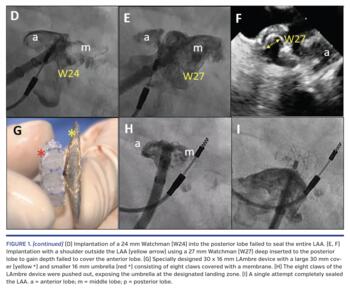

A 24 mm Watchman device (Boston Scientific) was initially chosen. However, the LAA could not be completely sealed despite multiple attempts at deploying the device from different lobes (Figure 1D; Video 1). A larger 27 mm Watchman device positioned deep into the posterior lobe with a shoulder hanging outside the LAA also failed to adequately seal the LAA (Figures 1E and 1F; Videos 2 and 3).

A specially sized LAmbre LAA occluder (Lifetech, Inc) with a 16 mm umbrella articulated to a 30 mm cover (Figure 1G) was designed to tackle this complex LAA anatomy, including the discrepancy between the orifice and landing zone in this case. The delivery sheath was positioned within the LAA without selective engagement of any lobes. The umbrella of the device was pushed and rolled out of the sheath, first allowing its eight claws to capture the trabeculae of the LAA for anchoring (Figure 1H; Video 4). The cover of the device was then unsheathed to occlude the orifice of the LAA with an inward indentation (Figure 1I; Videos 5 and 6). The multilobed LAA was completely occluded with a single attempt using the LAmbre device.